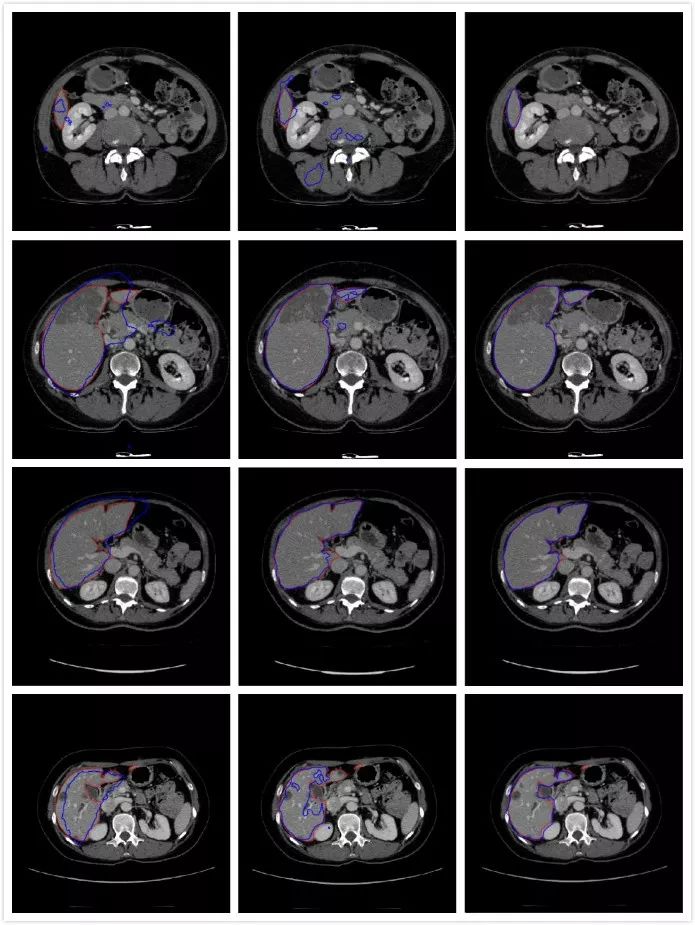

• 结果对比:本文算法对于各种形状的肝脏都有较高的分割准确率;FCN-8s对肝脏区域较大的图像分割准确率高,但结果较为细碎,分割较小的肝脏时,有许多冗余部分;U-Net能分割出肝脏所在区域的大致位置,但是无法获得肝脏的精确边界。

(a) U-Net分割图   (b) FCN-8s分割图 (c) 本文算法分割图

图3 不同算法分割图(注:红色轮廓为Ground Truth,蓝色轮廓为最终分割结果)